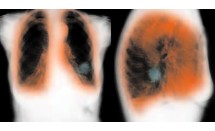

Les thérapies ciblées dans le traitement du cancer bronchique se développent de plus en plus. Par rapport à la chimiothérapie classique, elles présentent l'avantage d'être plus efficaces et moins toxiques.